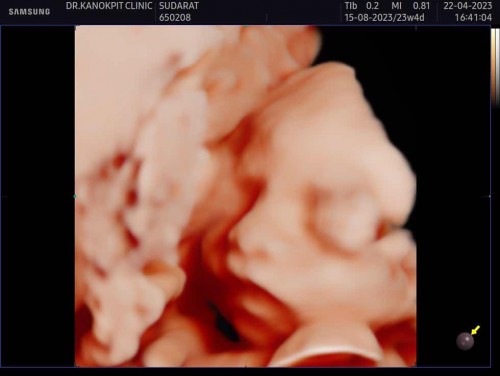

น้ำหนักลูกน้อยเท่าไหร่กันบ้างค่ะแม่ๆ บ้านนี้ 24 วีค 491g ค่ะ น้อยไปรึป่าวค่ะ แม่ขึ้นมา5 กิโลค่ะ อยากให้เบบี้จ้ำม่ำทานอะไรบำรุงดีค่ะ #ขอคำแนะนำหน่อยค่ะ ภาพซาวเมื่อวานจ้า สุดหล่อโชว์เจี๊ยว😀

ของเราตอนฝากครรภ์ล่าสุด 23สัปดาห์ 700 กรัมค่ะ น้องเป็นลูกหมู 🐷 55555 ปัจจุบัน 25+3 เจอหมออีกที 27 สัปดาห์คงจะเป็นโลแล้ว 🤣